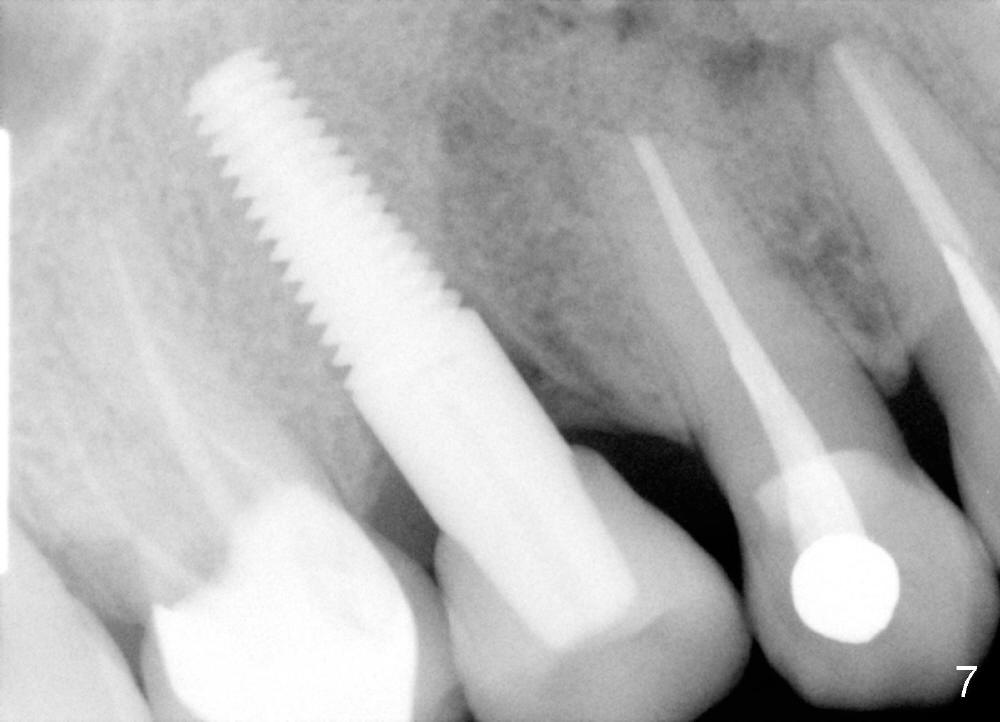

A single crown is cemented 3 months postop (Fig.6 C). Fig.7 is taken 6 months post cementation.

Eleven months post cementation, the patient returns for #3 crown recementation. The buccal plate atrophy over the implant is minimal (Fig.8).